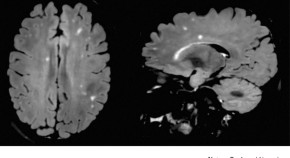

• The benefits of early treatment for multiple sclerosis (MS) place pressure on physicians to make the diagnosis early, thereby increasing the risk of misdiagnosis, which can have considerable consequences for patients and health-care systems. Solomon and Corboy examine the problem of MS misdiagnosis, including the probable causes and associated risks, and discuss how the tension between early diagnosis and misdiagnosis might be addressed.